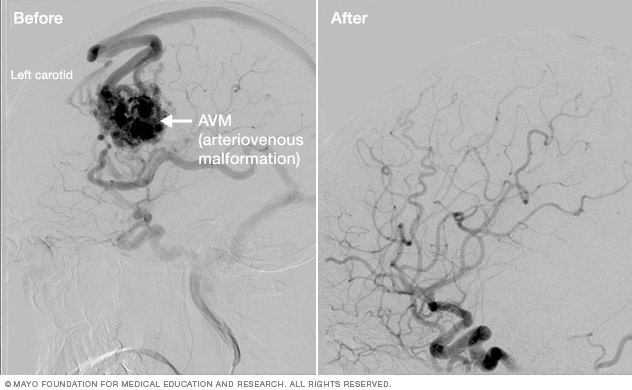

Brain AVM before and after Gamma Knife treatment

Brain arteriovenous malformation before Gamma Knife treatment (left) and 52 months after the procedure (right)